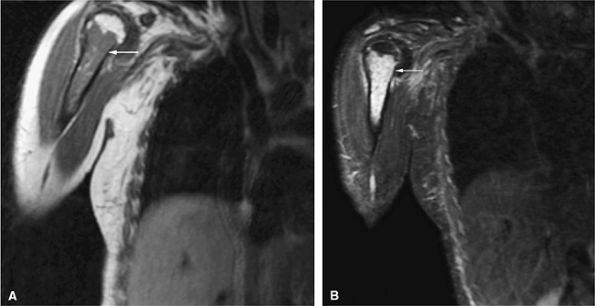

![]() |

FIGURE 13.64 ● Metastatic breast cancer involving the shoulder. (A) Diffuse hypointense marrow replacement is seen on a sagittal T1-weighted image (arrows). (B) Metastatic tumor is better visualized on the coronal STIR image (white arrows). Uninvolved marrow is hypointense (black arrows).